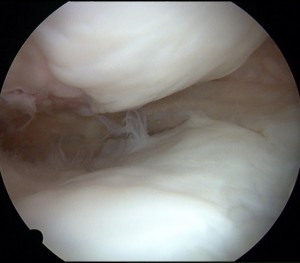

→最初の手術の時に完全に無くなっていた関節軟骨が手術後に修復されていることがあります。約4~5割の患者でこのような修復が見られます。軟骨が再生されるくらい膝関節の環境がよくなっていると考えられます。

関節軟骨が完全に消失した骨の表面(左図)が、術後1年で右図のように関節軟骨が再生され関節面が修復されている